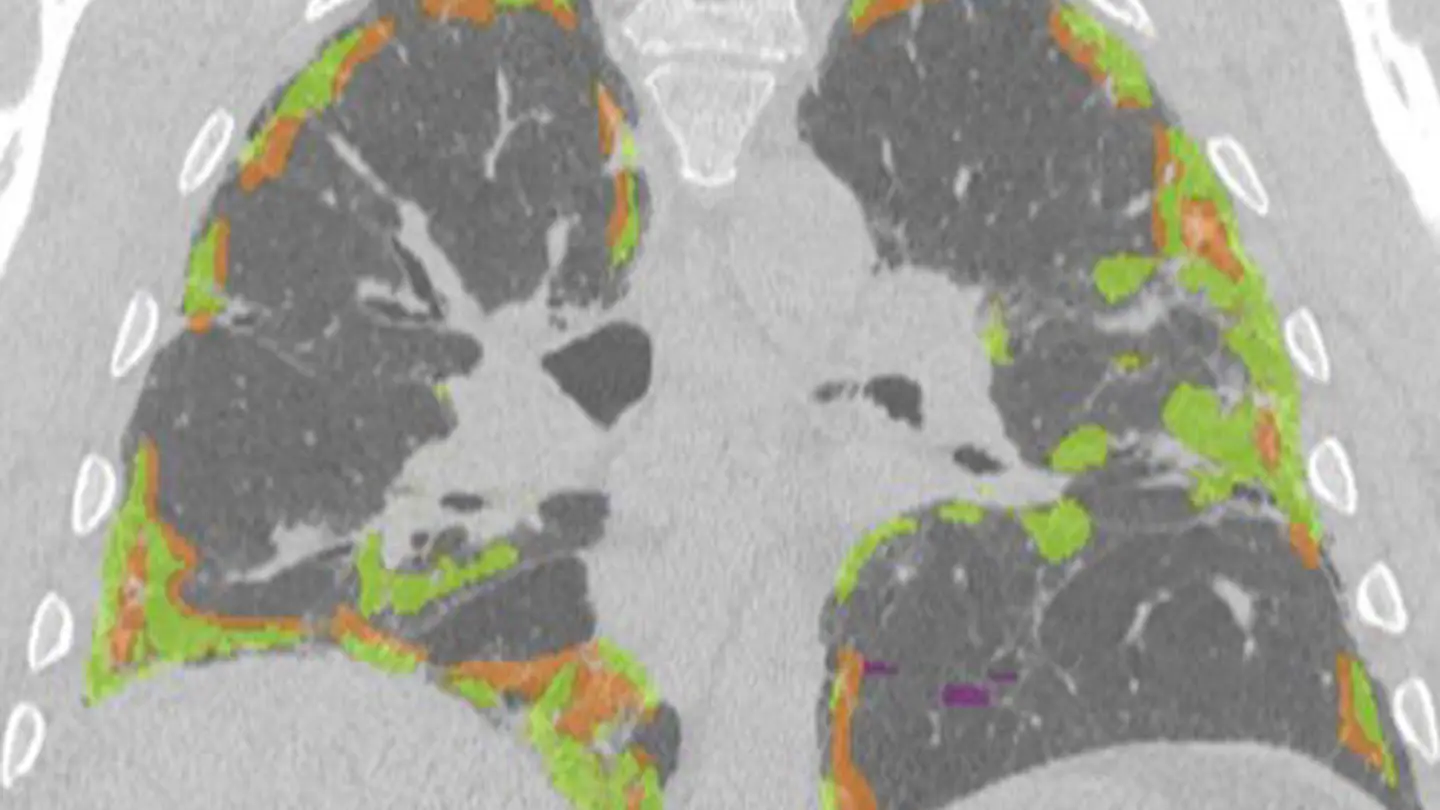

Our specialist lung assessment is used to diagnose a wide range of lung conditions utilising the expertise of specialist Cardiothoracic Radiologists and low-dose CT.

- Specialist report aided by Artificial Intelligence - for nodule detection and volumetry to guide management

Using the combined expertise of CT and specialist Cardiothoracic Radiologists, our specialist lung health assessment is used to assess and diagnose a wide variety of lung conditions. The assessment includes initial questions to evaluate your suitability for the assessment, lung cancer screening and a specialist report aided by Artificial Intelligence.